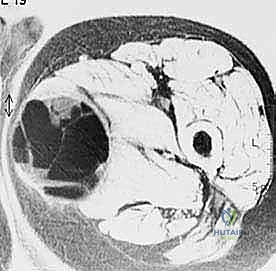

- الأشعة المقطعية (CT Scan): ضرورية لتقييم القشرة العظمية والتكلسات داخل الورم، وللبحث عن أي انتشار في الرئتين.

لضمان أخذ العينة من الجزء الأكثر تمثيلاً للورم وتجنب المناطق الميتة (Necrotic areas)، يستخدم الدكتور هطيف جهاز الأشعة المقطعية أو جهاز القوس المفلور (C-arm) لتوجيه الإبرة في الوقت الفعلي.